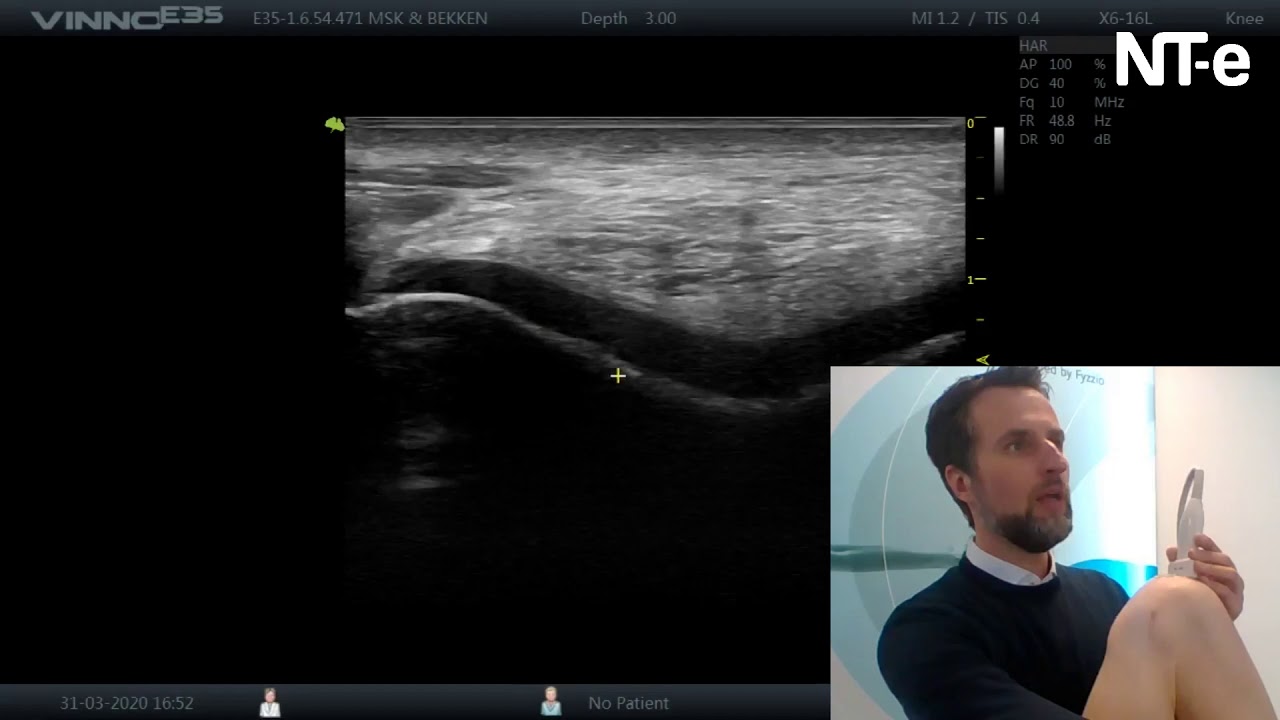

Echografie van het kraakbeen van de knie

In deze video bekijken we het kraakbeen van de knie met echogafie.